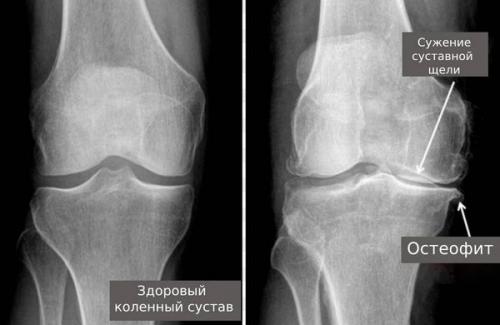

При дисплазиях нарушается ось суставов, вокруг которой совершаются движения . Это приводит к хронической перегрузке суставных поверхностей и дегенерации хряща. При последующем развитии остеоартроза изменяются свойства хряща, разрастаются суставные поверхности, формируются патологические наросты (остеофиты). На рентгенограмме остеофиты выглядят как блюдцеобразные расширения суставных поверхностей костей.

- при остеоартрозе суставная щель сужается и объём движений уменьшается из-за остеофитов;